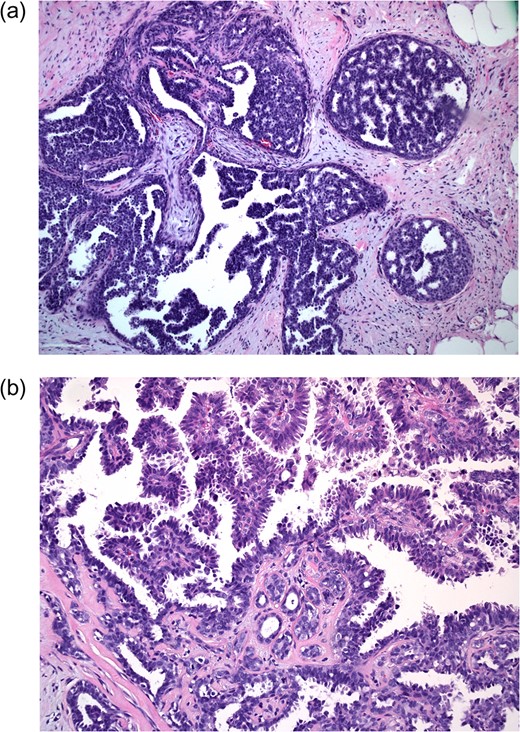

Bilateral mammogram demonstrated mild gynecomastia in both sides with no discrete mass or clusters of microcalcifications (Fig. 1). A follow-up ultrasound around the area of palpable concern did show a prominent duct with irregular contours at the 6:00 position in the left breast (Fig. 2). Excisional biopsy was recommended and a subareolar biopsy of the left breast was performed.

Diagnostic mammogram of the left (a) and right (b) breast demonstrates mild bilateral gynecomastia without discrete mass.